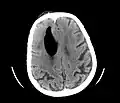

Additional images

Large pneumocephaly secondary to surgical wound -

Pneumocephaly